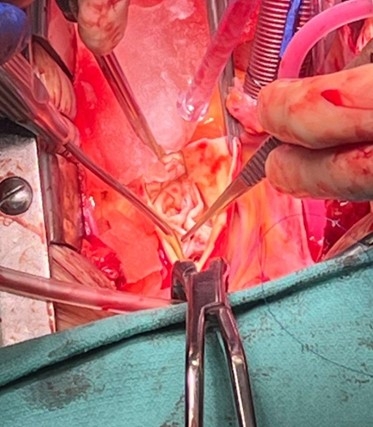

Abstract Body (Do not enter title and authors here): Description of Case: A 58-year-old man presented with progressive fatigue and dyspnea. Echocardiography showed mixed valve disease with severe aortic stenosis (AS), severe aortic regurgitation (AR), left ventricular hypertrophy, and preserved ejection fraction. Coronary angiography was normal. Chest computed tomography angiography revealed a quadricuspid aortic valve (QAV) with severe calcification and aneurysmal dilation of the ascending aorta to 47 mm. At the time of the operation, the quadricuspid valve was functionally bicuspid, with two raphes. An additional cusp was present between the right and left coronary cusps (Nakamura Type 1) with 2 equal larger cusps and 2 unequal smaller cusps (Hurwitz and Roberts Type F). The right and supernumerary cusps, and the left and non coronary cusps, were fused respectively. All cusps were significantly thickened and calcified. The degenerated valve was excised and replaced with a size 27 bioprosthetic valve. The ascending aorta was resected and replaced with a straight graft. Postoperative echocardiography confirmed a low mean gradient and normal function, and the patient had an uncomplicated recovery.